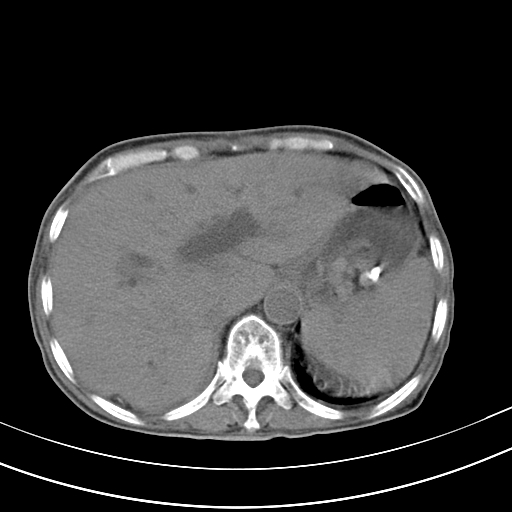

病人上腹部胀痛拌全身黄染八天

右侧少量胸水,胆囊增大,肝内胆管扩张,肝门部结构杂乱,建议增强。

肝内胆管及胰管扩张考虑为胰头区占位,肝门淋巴结增多,肝内多发低密度影,考虑为转移。门脉高压,脾大,胆囊大。

肝内胆管及胰管扩张,胰头增大考虑为胰头区占位,肝门淋巴结增多,考虑为转移。建议增强,脾大,胆囊大,壁厚,慢性胆囊炎。胃壁好像也增厚,且有一肿物。

1)考虑胰头癌并胆系低位梗阻;建议行ct增强扫描检查。2)慢性胆囊炎。3)脾大。4)少量腹水。5)双侧少量胸腔积液。